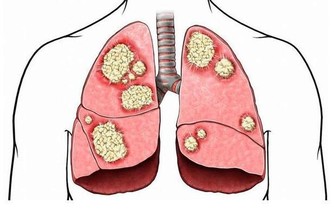

3、 尿酸

這五種毒素是女性衰老催化劑,必須盡快排出

尿酸是人體產生的一種物質,這種物質一般在人體中濃度是一樣的,但是如果出現濃度升高的話,可能出現對身體有一定的危害,人體尿酸偏高會對腎臟造成一定的影響,出現痛風性腎病,早期僅表現為間歇性蛋白尿,但只是隨著病情的發展,晚期可發生腎功能不全,部分患者會出現尿酸性腎結石當結石引起梗阻時導致腎積水,腎盂腎炎,腎積膿等。通常腎不好的女性會臉色發黃,嘴唇蒼白,自然也就更加顯老了。